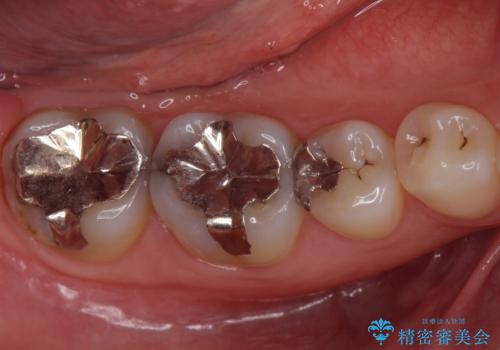

- 前歯を綺麗にしたいとのことで来院されました。

色調・適合ともに改善するために一度被せ物を外し、歯の形を整えた後に新しい被せ物を装着していきます。

歯ぐきの炎症を抑えつつ、被せ物と歯との境目がわからなくなるよう被せ物を装着しました。

審美性が大変改善されたことで患者様にもご満足いただけました。